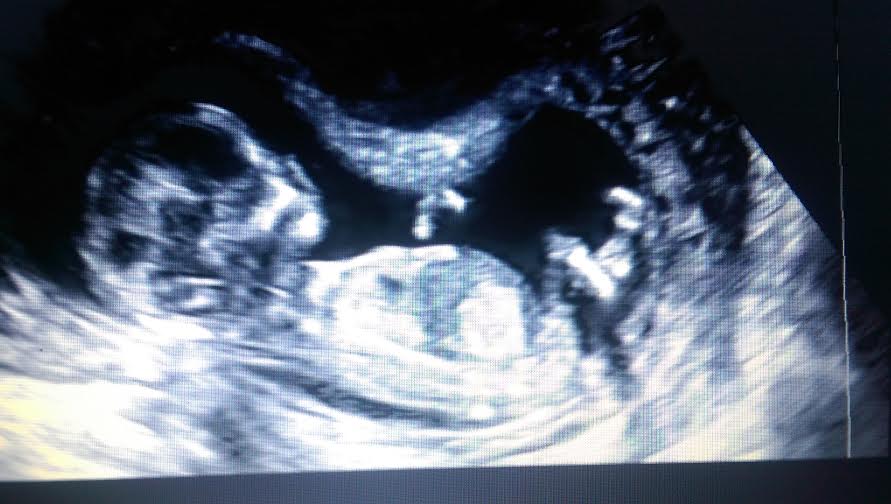

Hello! New here! Two boys already, and pregnant with our third. We went for an elective scan on Saturday, I was thirteen weeks plus two days. Tech was very confident with saying boy, but I know its still a bit early. Any chance of hearing girl later on?![]()

Still shot photo from video

The potty shot does look similar to my boys scans so I would say boy xx

The still potty shot looks like a boy

It looks like a boy but I am surprised they do elective scans for gender at 13 weeks.

Looks like a boy.

Definitely a boy after watching the video! Congrats!